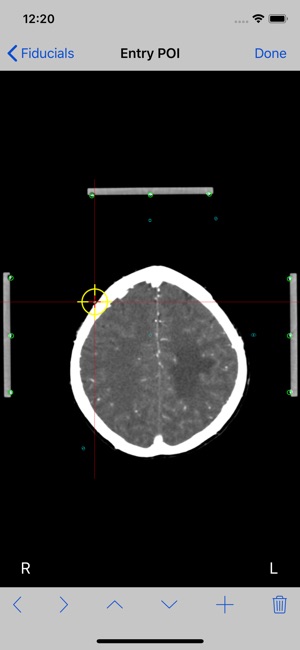

9. If Two Image method was selected, the entry point image will be shown. Tap the Done button.

Mark each fiducial on the image and tap the Done button. Mark the entry point and tap the Done button.

10.At this point the stereotactic parameters NT, SW, HW, NS and NV will be computed and displayed.